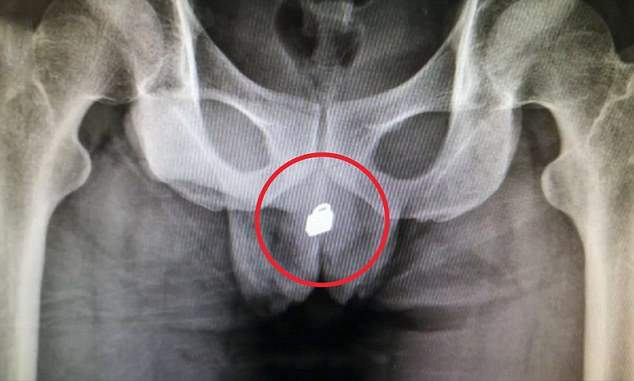

老二

・蠟筆

・原子筆、筆蓋

・筷子

・玩具尖銳的一端

・棒棒糖的棒子

・磁鐵

・螺絲起子

・第四台的銅軸電線

・髮夾

・結婚戒指

妹妹

・牙刷

・金屬塑料容器

・膠帶

・被逮捕時急忙塞進去的手機

・香水罐

・化妝棉

・內衣

・玩具扭蛋

・橡膠球

・湯匙